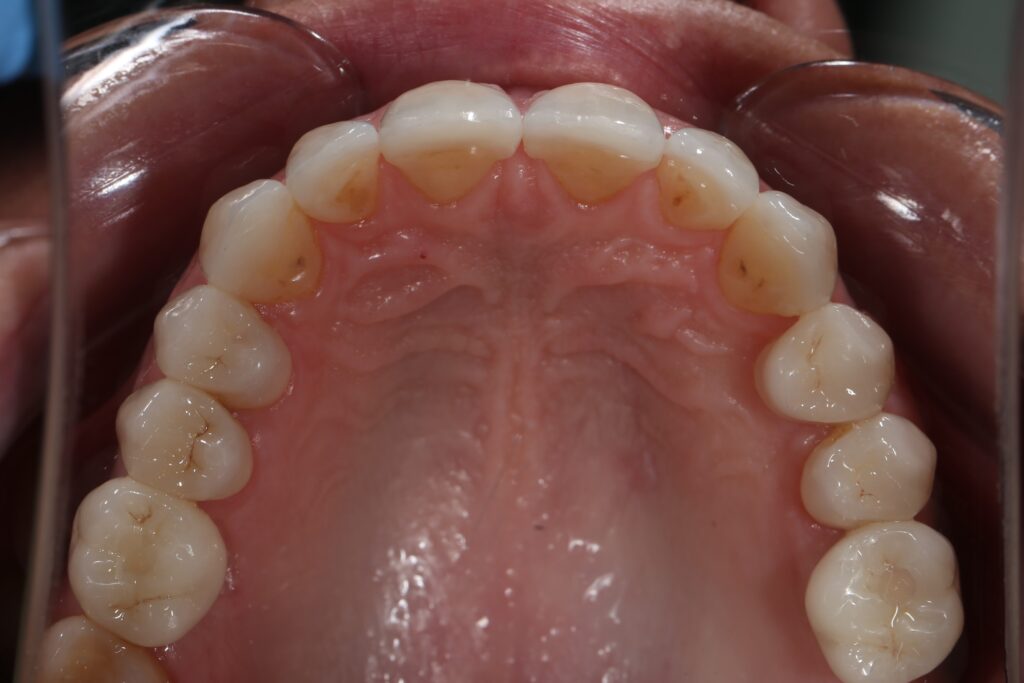

Результаты ортодонтической части

Была установлена брекет-система Damon Q. Срок лечения брекетами составил 11 месяцев.